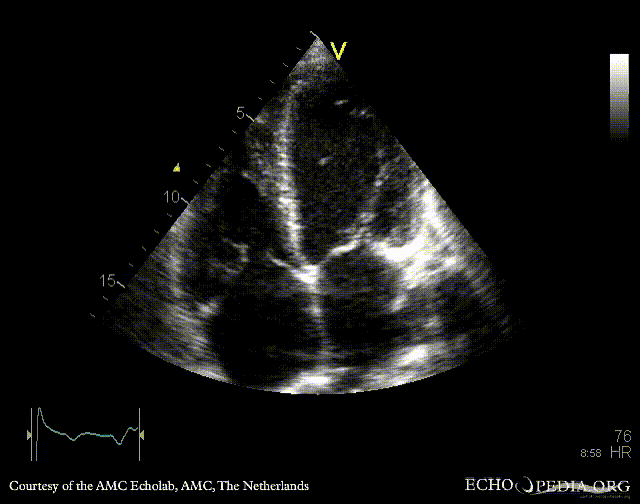

E00437.gif E00438.gif

A4CH: enlarged atria and ventricles A3CH: severe aortic and mitral regurgitation